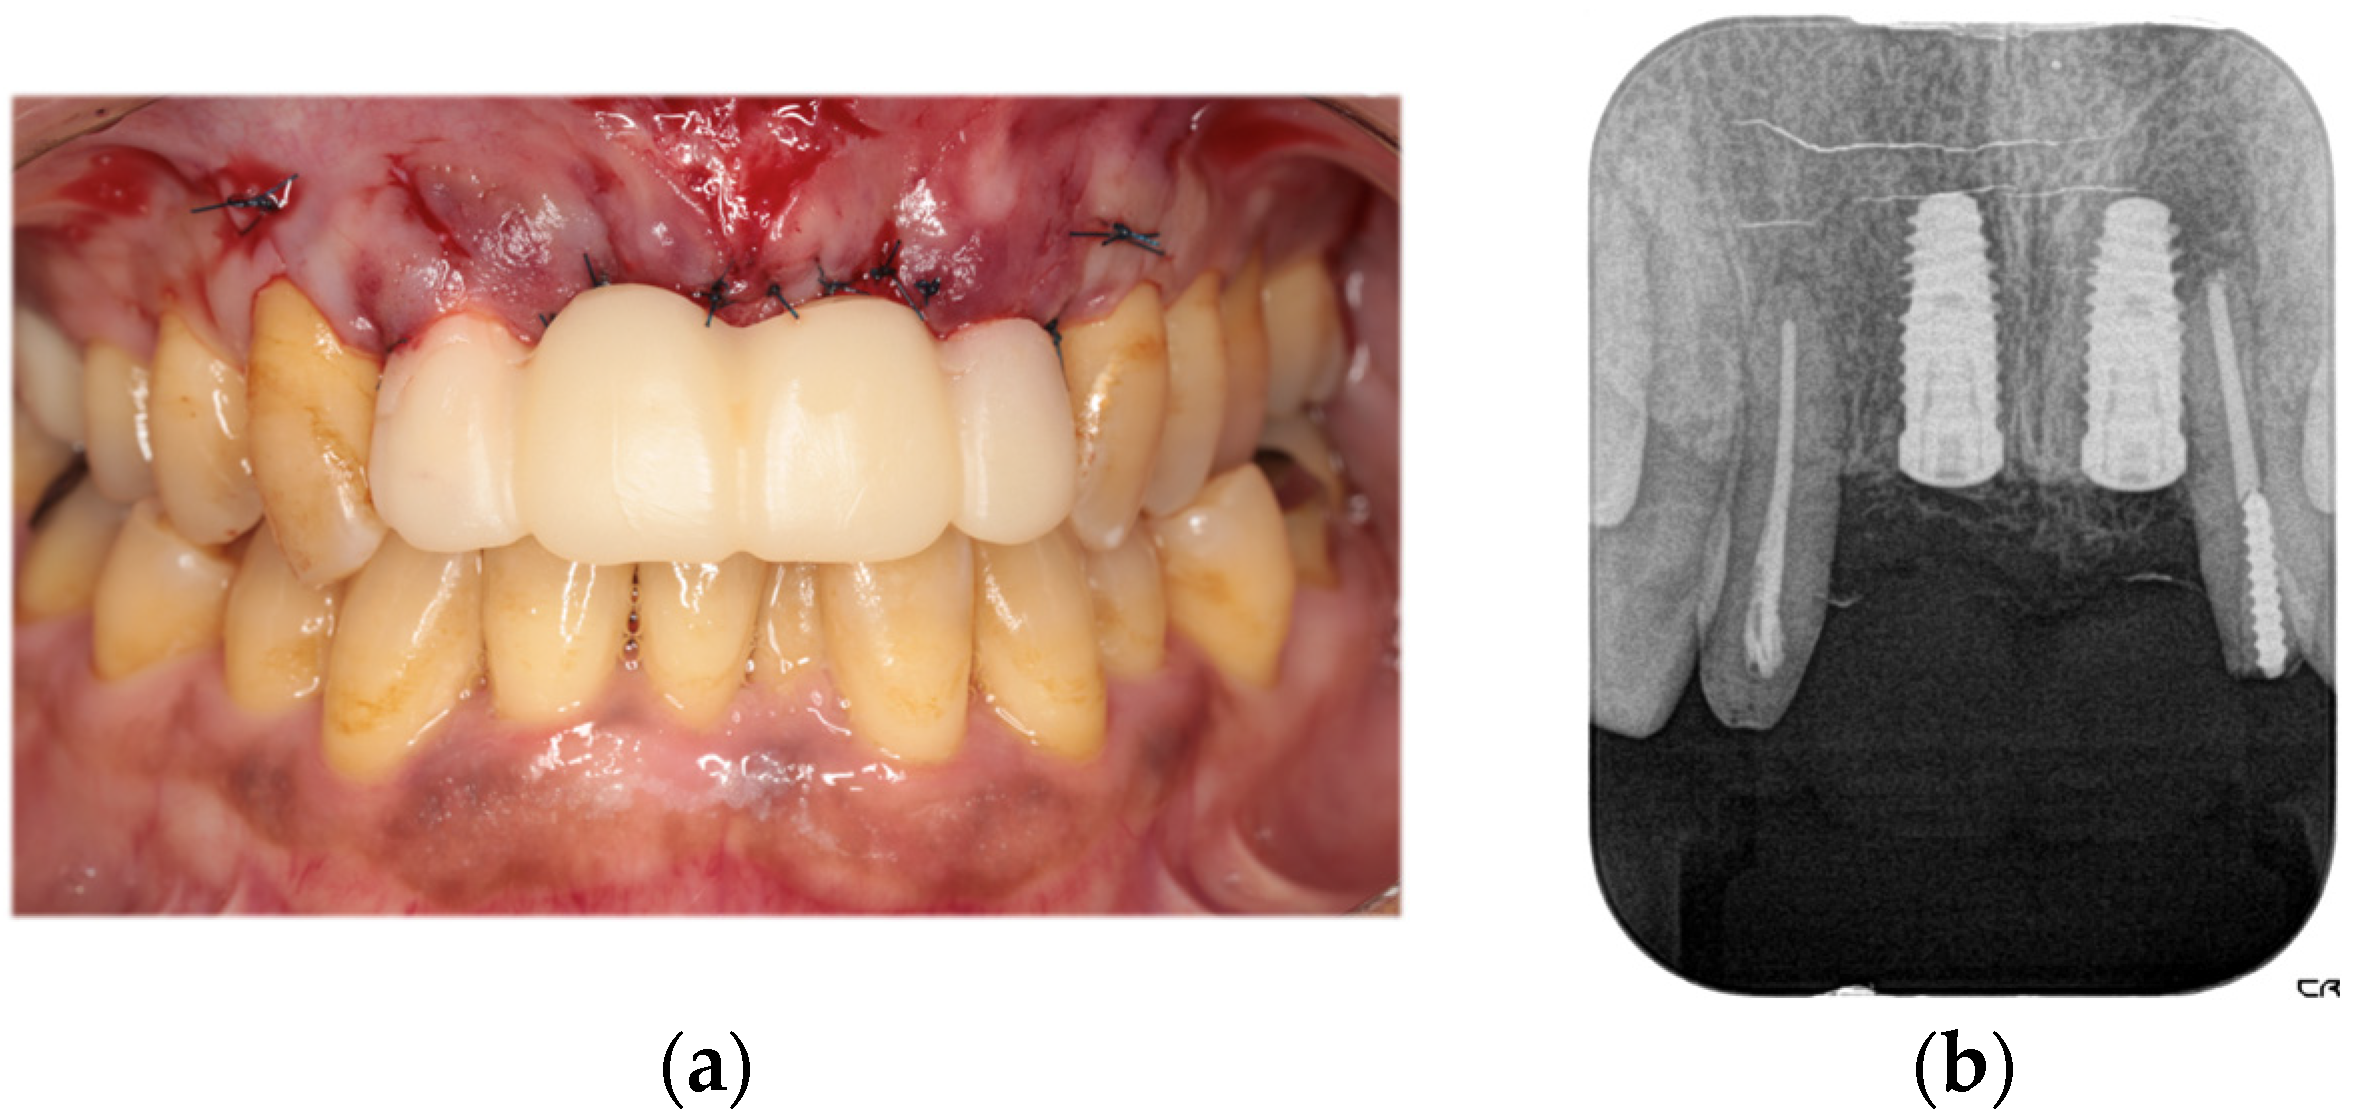

The second-stage implant exposure procedure was conducted in March 2017. Subsequently, a connective tissue graft was applied to enhance the soft tissue volume and improve aesthetic outcomes (Figure 9a). Provisional restorations were placed (Figure 9b), and orthodontic treatment was initiated (Figure 9c). The orthodontic treatment was completed in February 2018. Although the implant on the left side was in close proximity to the adjacent tooth, no clinical issues were observed around the implant or in the remaining teeth immediately after placement or during the provisional restoration period. Therefore, porcelain-fused-to-zirconia restorations were installed in the month (Panavia; Kuraray Noritake Dental Inc., Niigata, Japan) (Figure 10). Due to the low bone support of the maxillary bilateral lateral incisors and potential complications, screw retention was preferable to allow prosthetic device replacement. However, the structural complexity of the connection with the natural teeth makes screw retention difficult; therefore, the superstructure was cemented. Although provisional cementation would have been ideal for potential reprosthetics, luting cement was used to prevent intrusion of natural teeth. The patient’s oral aesthetics showed notable enhancement since the initial consultation, as depicted in Figure 11.

Figure 10. Right-lateral (a), frontal (b), and left-lateral (c) views and dental radiograph (d) obtained immediately after the cementation of the final prosthesis.

Diagnostics 15 00765 g010